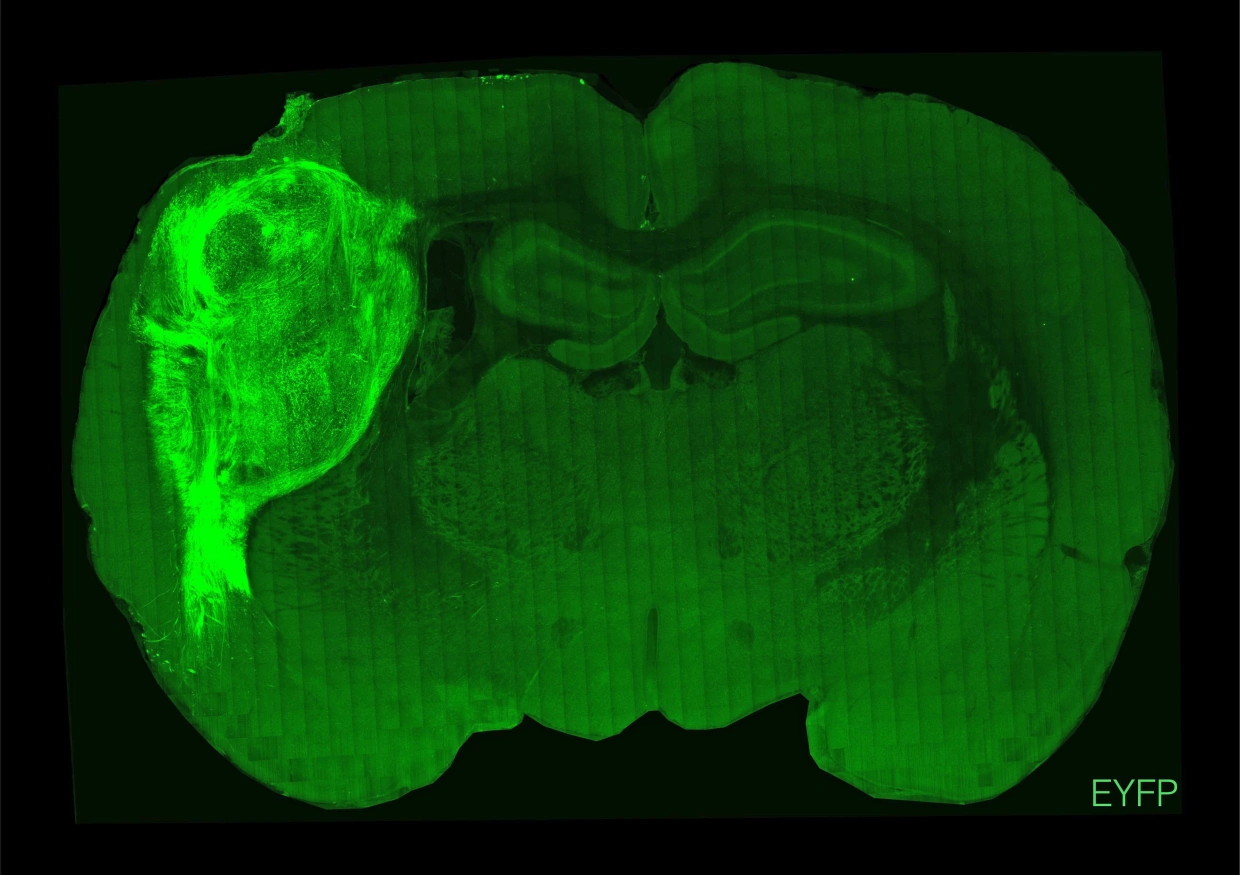

Yedi yıl önce Stanford Üniversitesi’ndeki araştırmacılar bir deneye başladılar. Buna göre, bir laboratuvarda kök hücrelerden insan beyninin minyatür, basitleştirilmiş versiyonlarını büyütmeye başladılar ve daha sonra bu dokuyu yeni doğan farelerin beyinlerine enjekte ettiler.

Nature dergisinde dün yayınlanan sonuçlar, beyin benzeri insan dokusunun fare dokusuyla bütünleştiğini ve ardından olgunlaşmaya devam ettiğini gösterdi. Bu beyin hücrelerinin de farelerin davranışlarını etkilediği görüldü.

Araştırmacılar, insan dokusunu farelerin dokunma veya ağrı gibi duyusal bilgileri alan ve işleyen bölgesi olan somatosensoriyel kortekslerine enjekte etti. Yaklaşık iki haftalık eğitimden sonra araştırmacılar insan nöronlarını, mavi ışık lazerleri kullanarak her uyardıklarında, fareler su aramak için bir musluğu yalamaya başladılar. Araştırmacılar ayrıca farelerin bıyıklarını uyarmak için hava kullandılar ve ardından insan nöronlarının nasıl tepki verdiğini gözlemlediler.

Nakillerden sonra, insan nöronlarının yaklaşık sekiz ay içinde orijinal boyutlarının altı katına kadar büyüdüğünü ve fare beyinlerinin tek bir yarısının kabaca üçte birini oluşturduğunu söyledi.